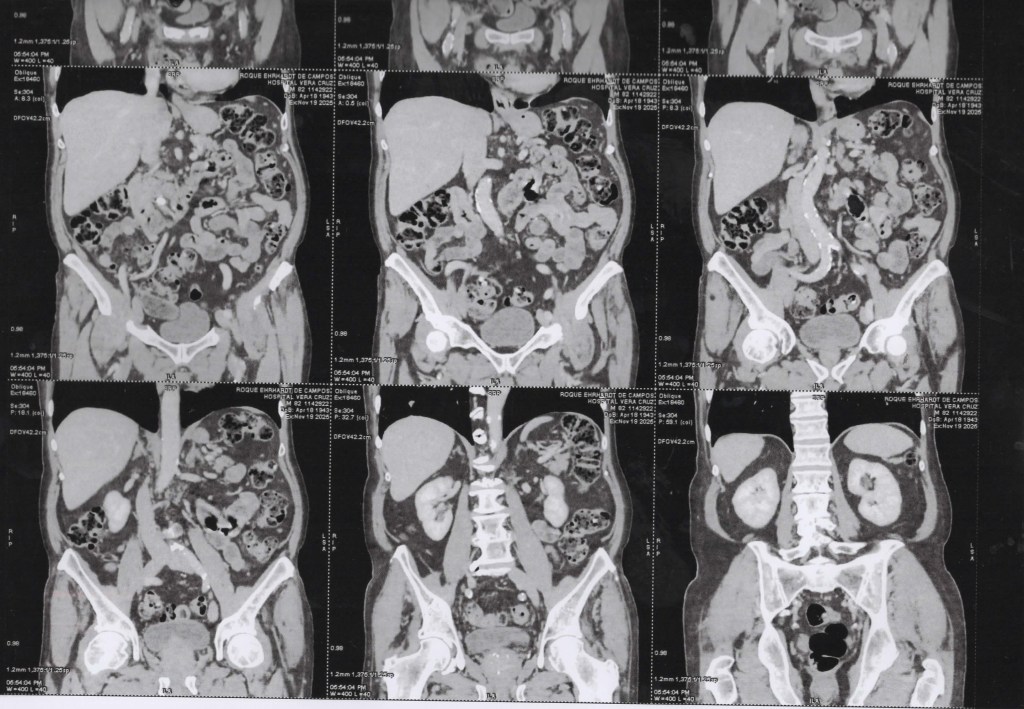

Abdome 19/11/2025 Vista Axial

(TC) de Abdômen com cortes axiais, em janela de tecidos moles, com contraste 19 11 2025